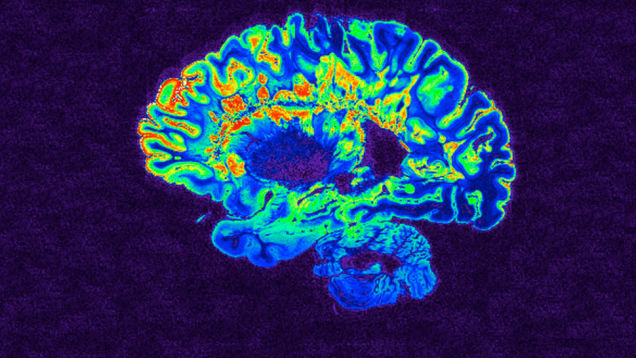

By prodding a tiny brain region linked to consciousness, scientists caused anesthetized monkeys to suddenly become awake and alert. This fascinating result is providing new clues about the brain and how it produces conscious awareness—insights that could potentially lead to therapies for patients trapped in a coma.